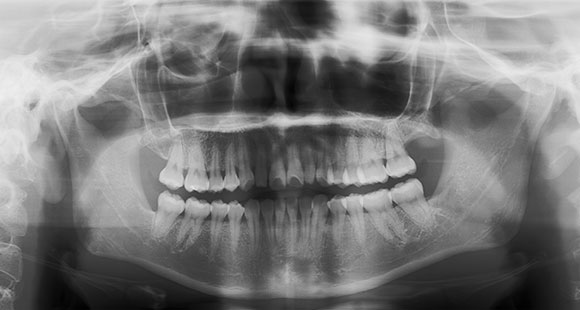

パノラマ

上下の歯列全体を1枚の写真に収めます。

これで分かるのは、歯や歯根、親知らず、骨の状態、虫歯や歯周病などといった口腔内の状態を確認することができます。

パノラマレントゲン